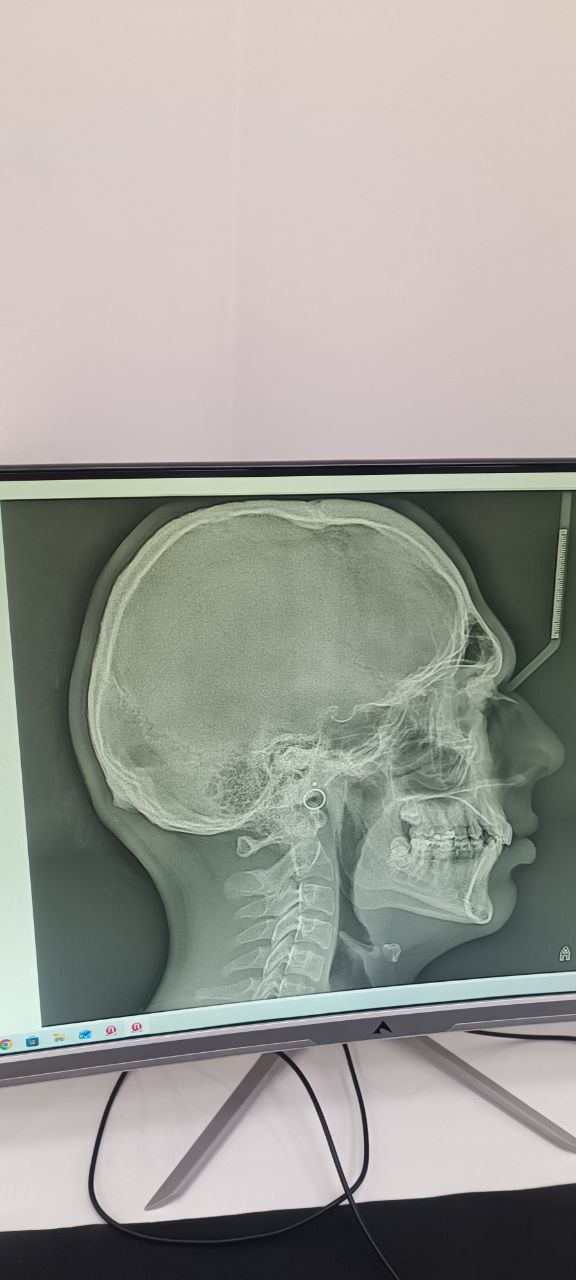

Over for my maxilla?

• IMG_20260226_123204_606.jpg

IMG_20260226_123204_606.jpg